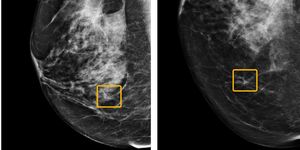

Formel 1 börjar testa AI-system Foto: Jen Ross / Wikipedia Formel 1 börjar testa AI-system Som ska hålla koll så att förarna håller sig på banan FIA, organisationen bakom Formel 1, kommer att börja testa ett system som med hjälp av datorsyn och artificiell intelligens ska kontrollera så att förarna håller sig inom banans gränser och inte kör över linjerna som markerar banans sträckning. Systemet kommer att användas i kombination med mänskliga observatörer. Tanken är att systemet ska hitta solklara fall som visar om föraren håller sig på banan medan lite mer tveksamma fall ska granskas av människor. Förhoppningen är att detta ska leda till att antalet bedömningar där människor är inblandade ska minska markant och göra processen snabbare. Systemet i fråga ska efterlikna sådana som används för att utesluta fall vid till exempel misstänkt förekomst av cancer hos människor. FIA skriver:"What they’ve concluded is they don’t want to use the Computer Vision to diagnose cancer, what they want to do is to use it to throw out the 80% of cases where there clearly is no cancer in order to give the well trained people more time to look at the 20%. And that’s what we are targeting."Reuters skriver att FIA vid Austrian Grand Prix i juli fick granska 1200 potentiella banöverträdelser manuellt. Förhoppningen är att få ner detta till cirka 50 stycken per lopp med hjälp av det nya AI-systemet. fia.com Samhälle, AI, formel 1, f1, racing, artificiell intelligens Via reuters.com Mammografi med AI kan hitta 20 procent fler bröstcancerfall Och minska arbetsbördan med 44 procent Tumnagel 60.3° 0 Blodprov kan eventuellt upptäcka tolv olika cancerformer Blodet analyseras med en artificiell intelligens Tumnagel 70.4° 0 AI ska hitta hitta cancer i munhålan Nytt forskningsprojekt inlett på Blekingesjukhuset Tumnagel 45.1° 0 AI-näsa kan sniffa upp patienter som riskerar att få cancer Blir smidigare och billigare än endoskopi Tumnagel 49.1° 0 Google har en AI som kan upptäcka bröstcancer Gör detta bättre än mänskliga läkare Tumnagel 60.1° 0 AI lika bra på att upptäcka risk för bröstcancer som en läkare Kan kontrollera bröstvävnads täthet Tumnagel 46.2° 0 AI är bättre än människor på att upptäcka hudcancer Framtidens sjukvård redan idag Tumnagel 57.7° 0 38.1° 0 Wille Wilhelmsson Wille Wilhelmsson